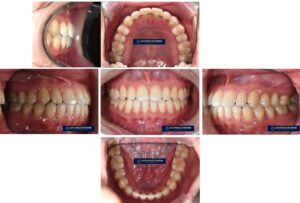

망우동 교정 치과 전치부 총생과 과개교합으로 돌출된 얼굴, 발치교정을 통한 개선 과정 알아봅시다.

안녕하세요, 망우동 교정 치과 김정은 원장입니다. 전치부는 대화를 하거나 웃을 때 먼저 시선이 닿는 부위로치아의 배열 하남나으로도 얼굴 인상과 심미적 이미지에큰 영향을 주게 됩니다. 특히 앞니가 겹쳐 있거나 깊게 물리는…